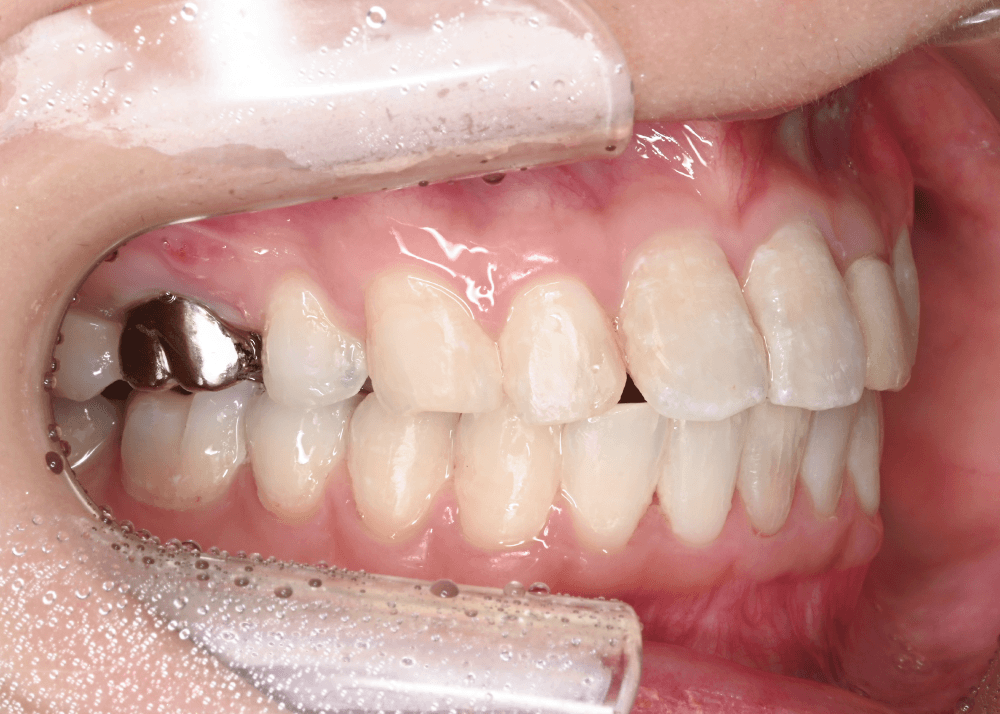

治療後の変化

治療後は、舌側に倒れていた前歯の傾きが改善しています。

・上下前歯のなす角(Interincisal angle)

138° → 125°

前歯のポジションが適正化されたことで、スマイル時に奥まって見えていた歯の見え方が改善し、より自然な印象になっています。

また、唇を内側から支える「口唇サポート」が回復し、横顔の印象にも変化がみられました。

治療前後の写真比較

治療後(32か月)